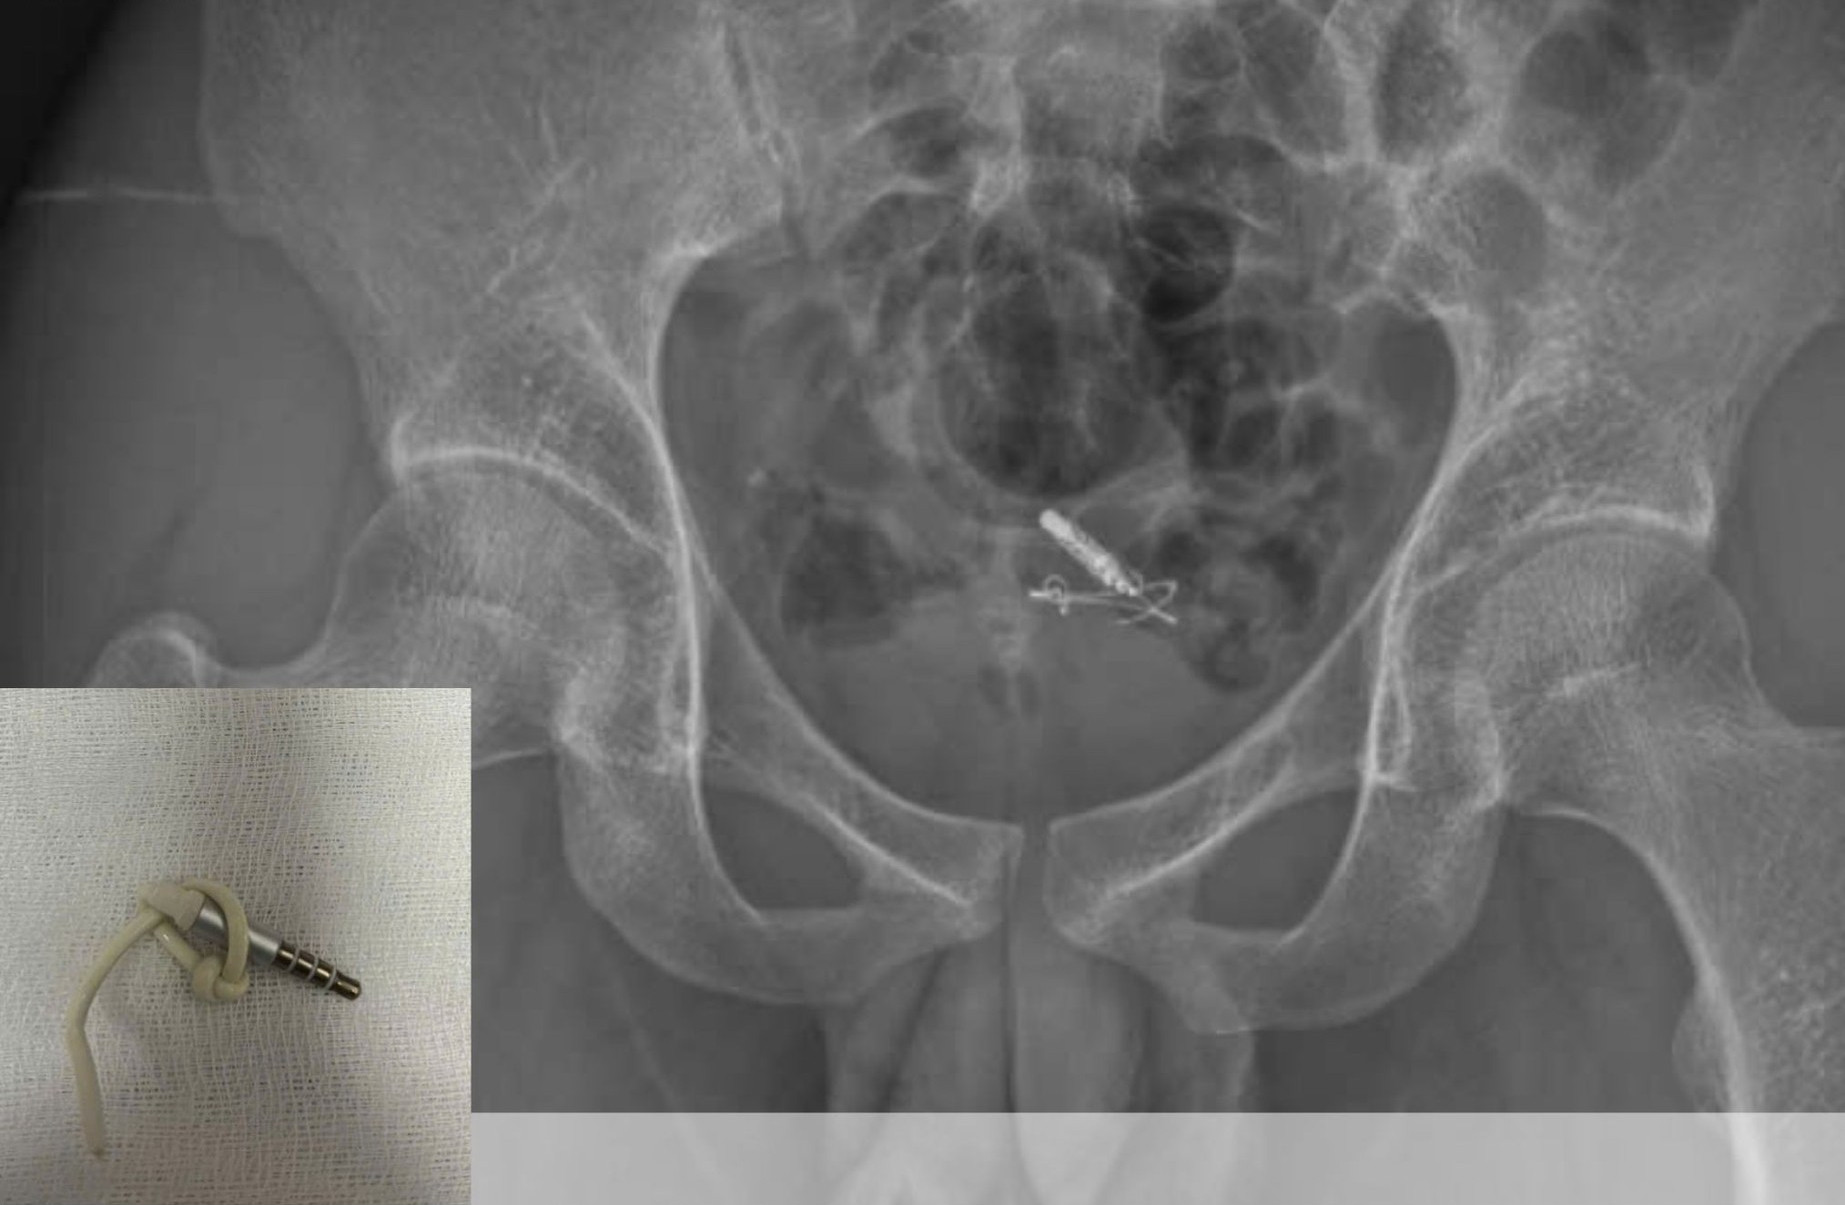

Hình ảnh dị vật lấy ra là đoạn dây cáp tai nghe kèm 1 jack cắm. Ảnh: Bệnh viện cung cấp

Tại bệnh viện, bác sĩ xác định đây là trường hợp dị vật gây tổn thương niệu đạo. Kết quả chụp X-quang và siêu âm cho thấy dị vật nằm trọn trong bàng quang.

Kíp phẫu thuật đã tiến hành nội soi gắp dị vật thành công, lấy ra một đoạn dây cáp tai nghe kèm 1 jack cắm 3,5 mm dài khoảng 10 cm, bảo tồn nguyên vẹn cấu trúc bàng quang và niệu đạo.